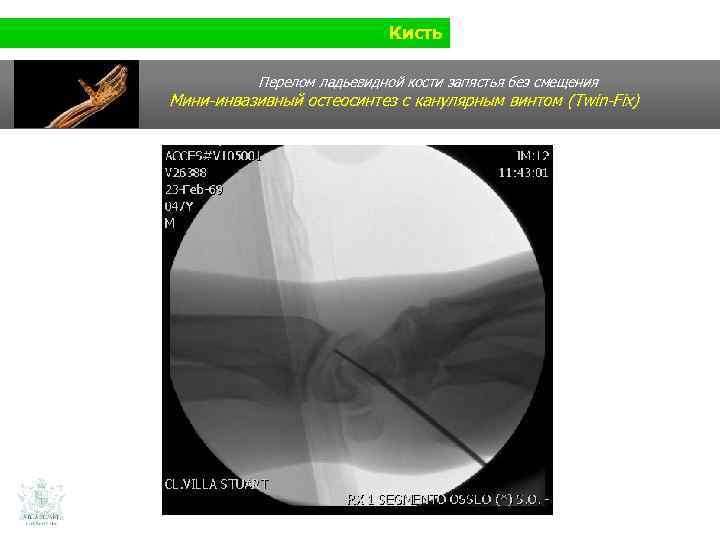

Кисть Перелом ладьевидной кости запястья без смещения

Кисть Перелом ладьевидной кости запястья без смещения Мини-инвазивный остеосинтез с канулярным винтом (Twin-Fix)